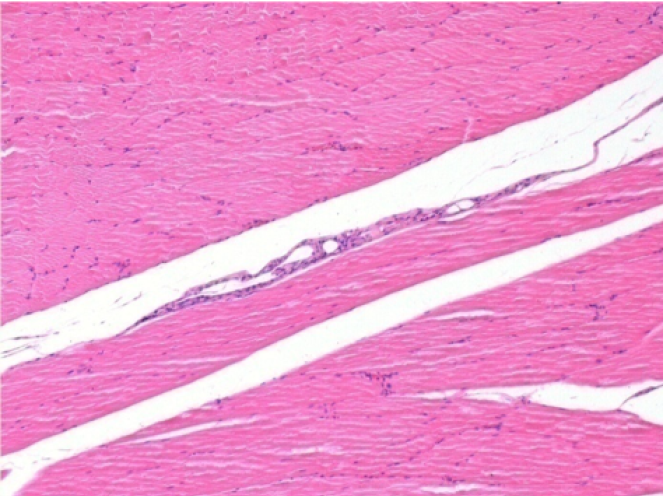

3 meses (D90) después de la inyección de Endopeel 0.1ml en el músculo pretibial derecho.

09